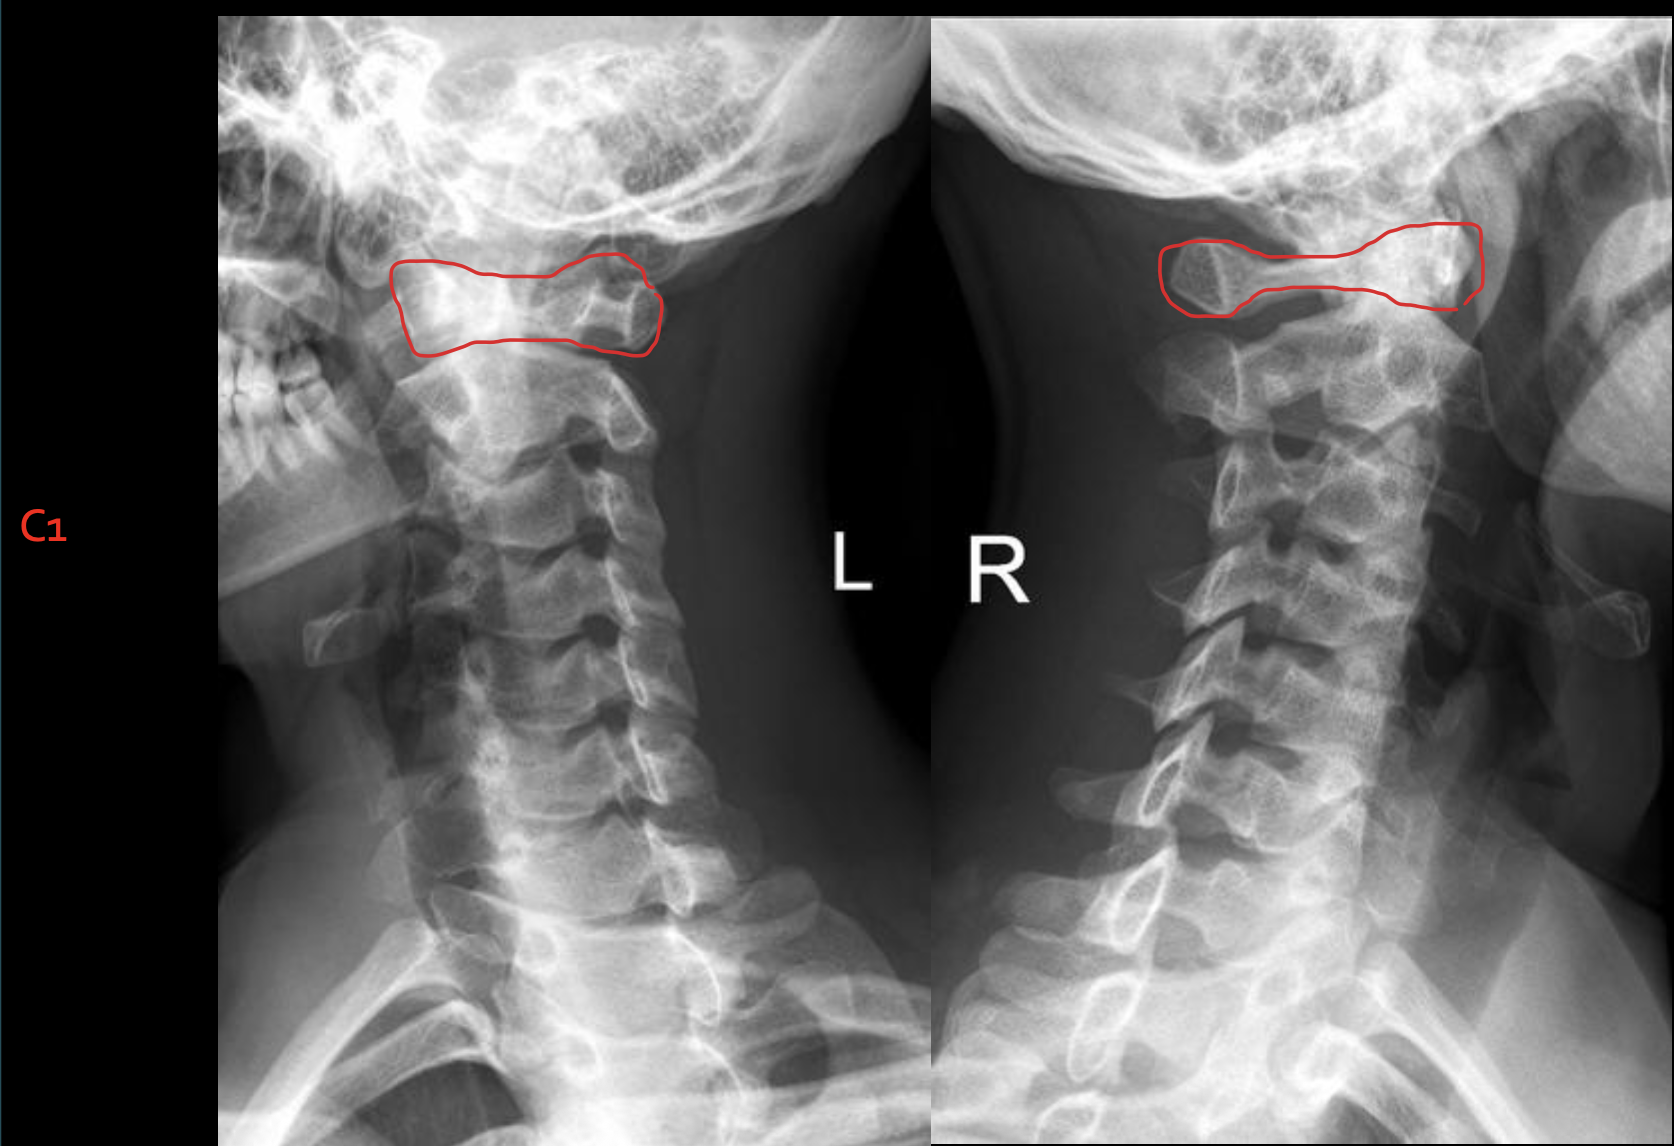

C1

寰椎前结节

C1 anterior tubercle

寰椎后弓及后结节

C1 posterior arch & tubercle

寰椎前弓

Anterior arch of C1